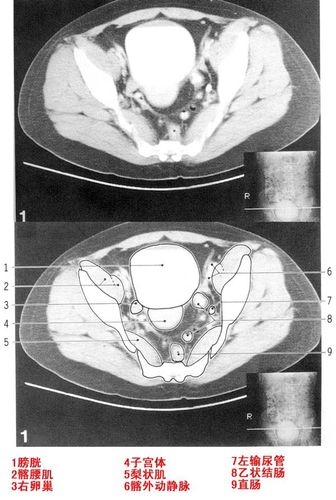

盆腔ct定位线图片

盆腔ct定位线图片,ct定位线身体定位图

女性盆腔ct解剖

盆腔ct解剖图

女性盆腔ct解剖图

女性盆腔ct断层解剖图

正常女性盆腔ct解剖图